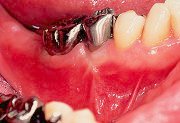

1

| 術直前にアタッチメントレベルを計測しておく(この時点で歯肉は可及的に健康な状態にしておく)。 |

2

| 歯肉弁を剥離したところ、頬側に II級根分岐部病変が認められた。 分岐部内の肉芽を完全に除去し、根面をルートプレーニングし終わった状態。 |